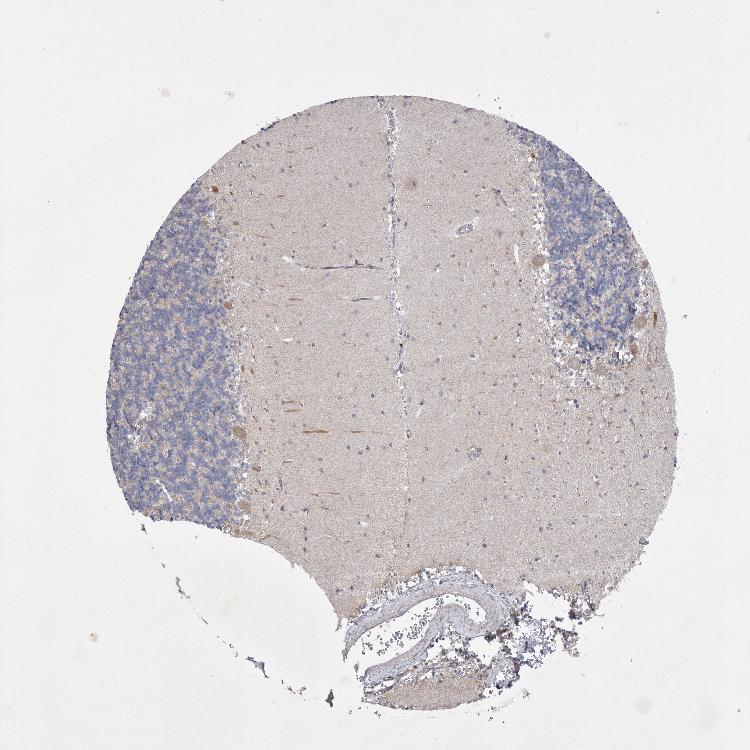

CEREBELLUM - Antibody stainingi

Antibody staining in the annotated cell types in the current human tissue is reported as not detected, low, medium, or high, based on conventional immunohistochemistry profiling in selected tissues. This score is based on the combination of the staining intensity and fraction of stained cells.

Each image is clickable and will lead to virtual microscopy that enables deeper exploration of all samples and also displays staining intensity scores, fraction scores and subcellular localization as well as patient and tissue information for each sample.

Antibody HPA027766

Purkinje cells Medium

Cells in granular layer Not detected

Cells in molecular layer Not detected